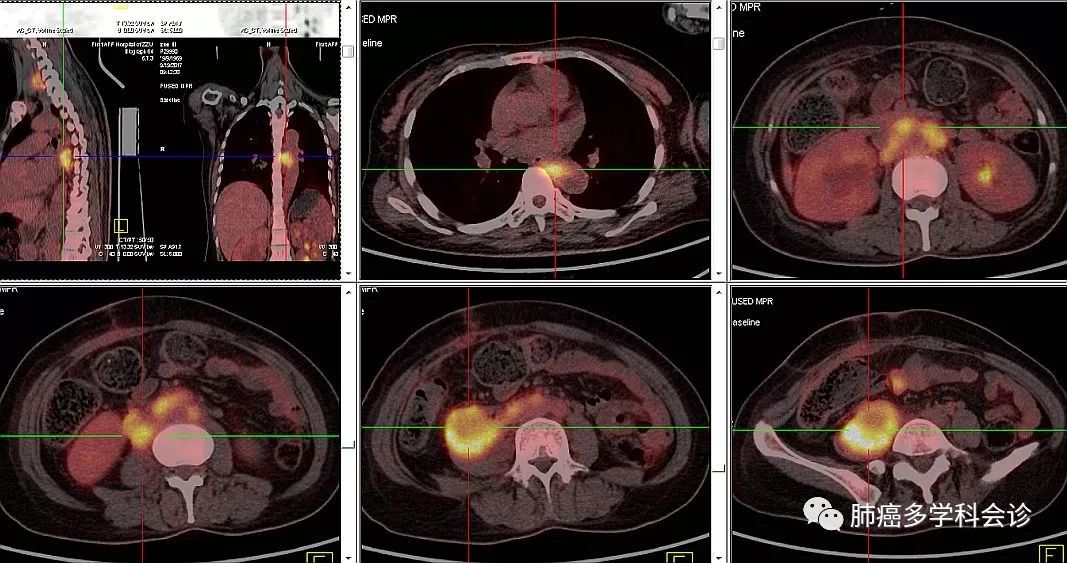

PET-CT:胸中段食管局部粘膜增厚代谢活跃,考虑食管癌;左颈Ⅲ-Ⅴ区、左侧锁骨上区、膈上后群、腹主动脉周围及双侧髂血管旁多发淋巴结肿大代谢活跃,右侧腰大肌旁软组织肿块代谢活跃,考虑转移;右侧腰大肌受侵,右侧输尿管疑受侵。